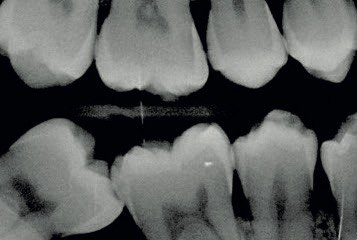

2. What surface require restoration?